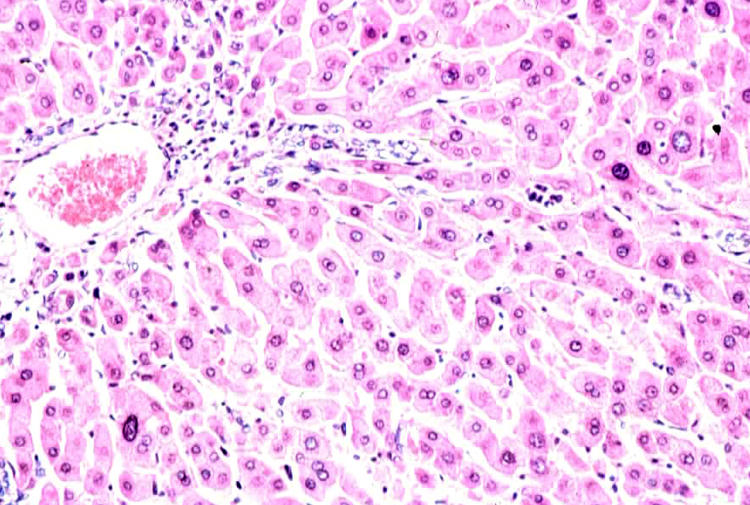

Which of these is the best definition of pleomorphism? (it can be visualized in the photo, which is from the liver of a woodchuck!)

All of these choices define pleomorphism!